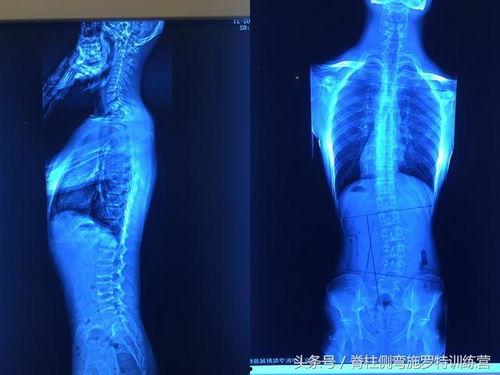

首先,让我们来了解一下脊柱弯曲。脊柱弯曲,医学上称为脊柱侧弯,是指脊柱在X光片上呈现的侧弯或后凸。这种弯曲不仅影响外观,还可能引起疼痛、呼吸困难等问题。据统计,全球约有5%的成年人患有脊柱弯曲。